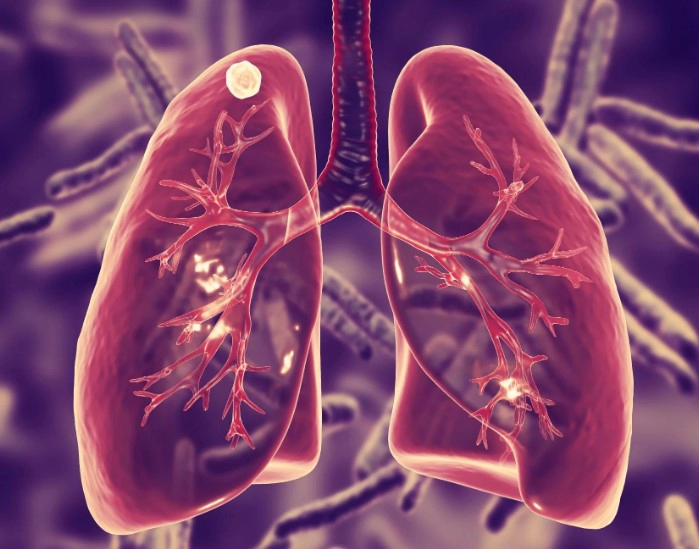

잠복결핵이란

잠복결핵은 결핵균에 감염되어 있지만 증상이 나타나지 않는 상태를 말합니다. 이런 사람들은 일반적으로 감염의 초기 단계에서 결핵 질환을 전파하지 않으며, 결핵이 활성화되기 전까지 아무 증상없는 상태를 유지합니다.

이는 마치 결핵균이 "잠자고 있는" 상태와 비슷하다고 볼 수 있으며, 이 때문에 이를 '잠복 결핵'이라고 부릅니다. 약 10%의 잠복 결핵 환자들이 평생 중 어느 시점에서든 결핵으로 질환을 발병하게 됩니다. 그리고 이 비율은 면역 체계가 약화된 사람들, 예를 들면 HIV 감염자나 특정 약물을 복용하는 사람들에서는 훨씬 높아집니다.